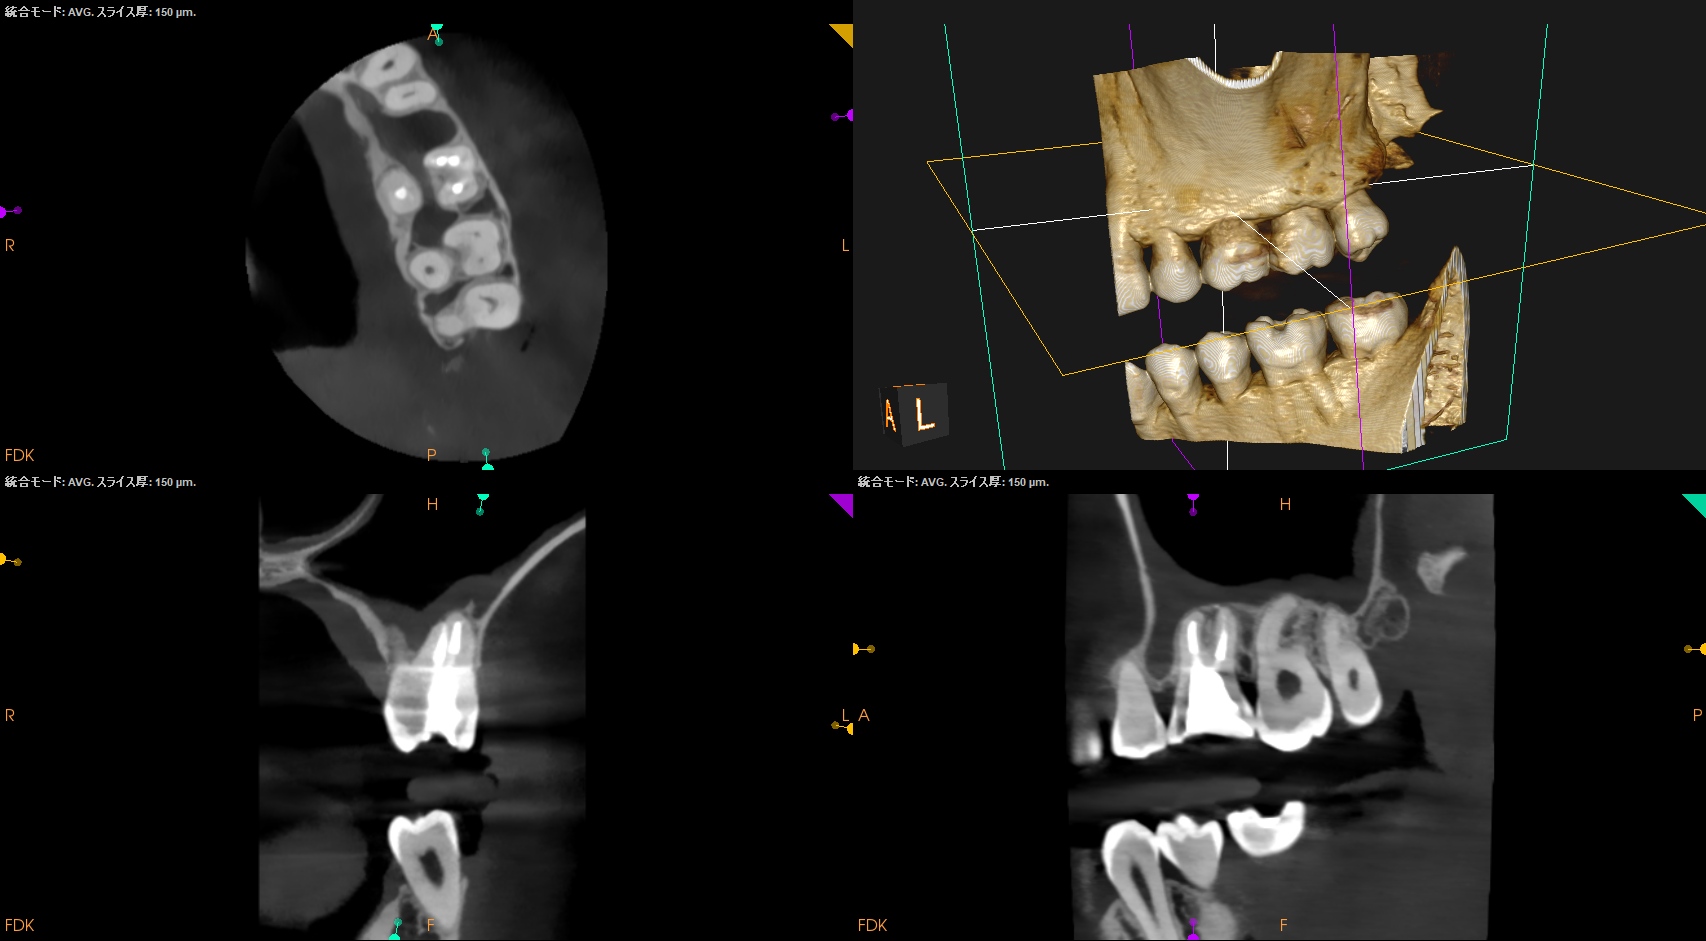

#14 Re-RCT 6yr recall(2026.1.27)

MB

MB2

DB

P

根尖病変は消失した。

また、再治療直後に根尖孔外へとはみ出たGutta Percha Pointの残渣も消失した。